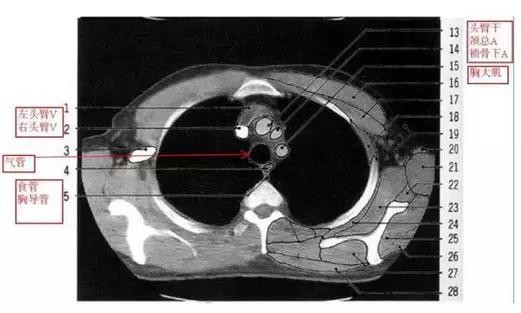

详尽的胸部CT影像示意图

胸部的CT是通过X线计算机体层摄影(CT)对胸部进行检查的一种方法。正常胸部CT层面较多,每一层面结构所表现的图像不同。下面是胸部CT图文示意图,可帮助临床医生详细了解CT结构。我们一起来看一下吧。